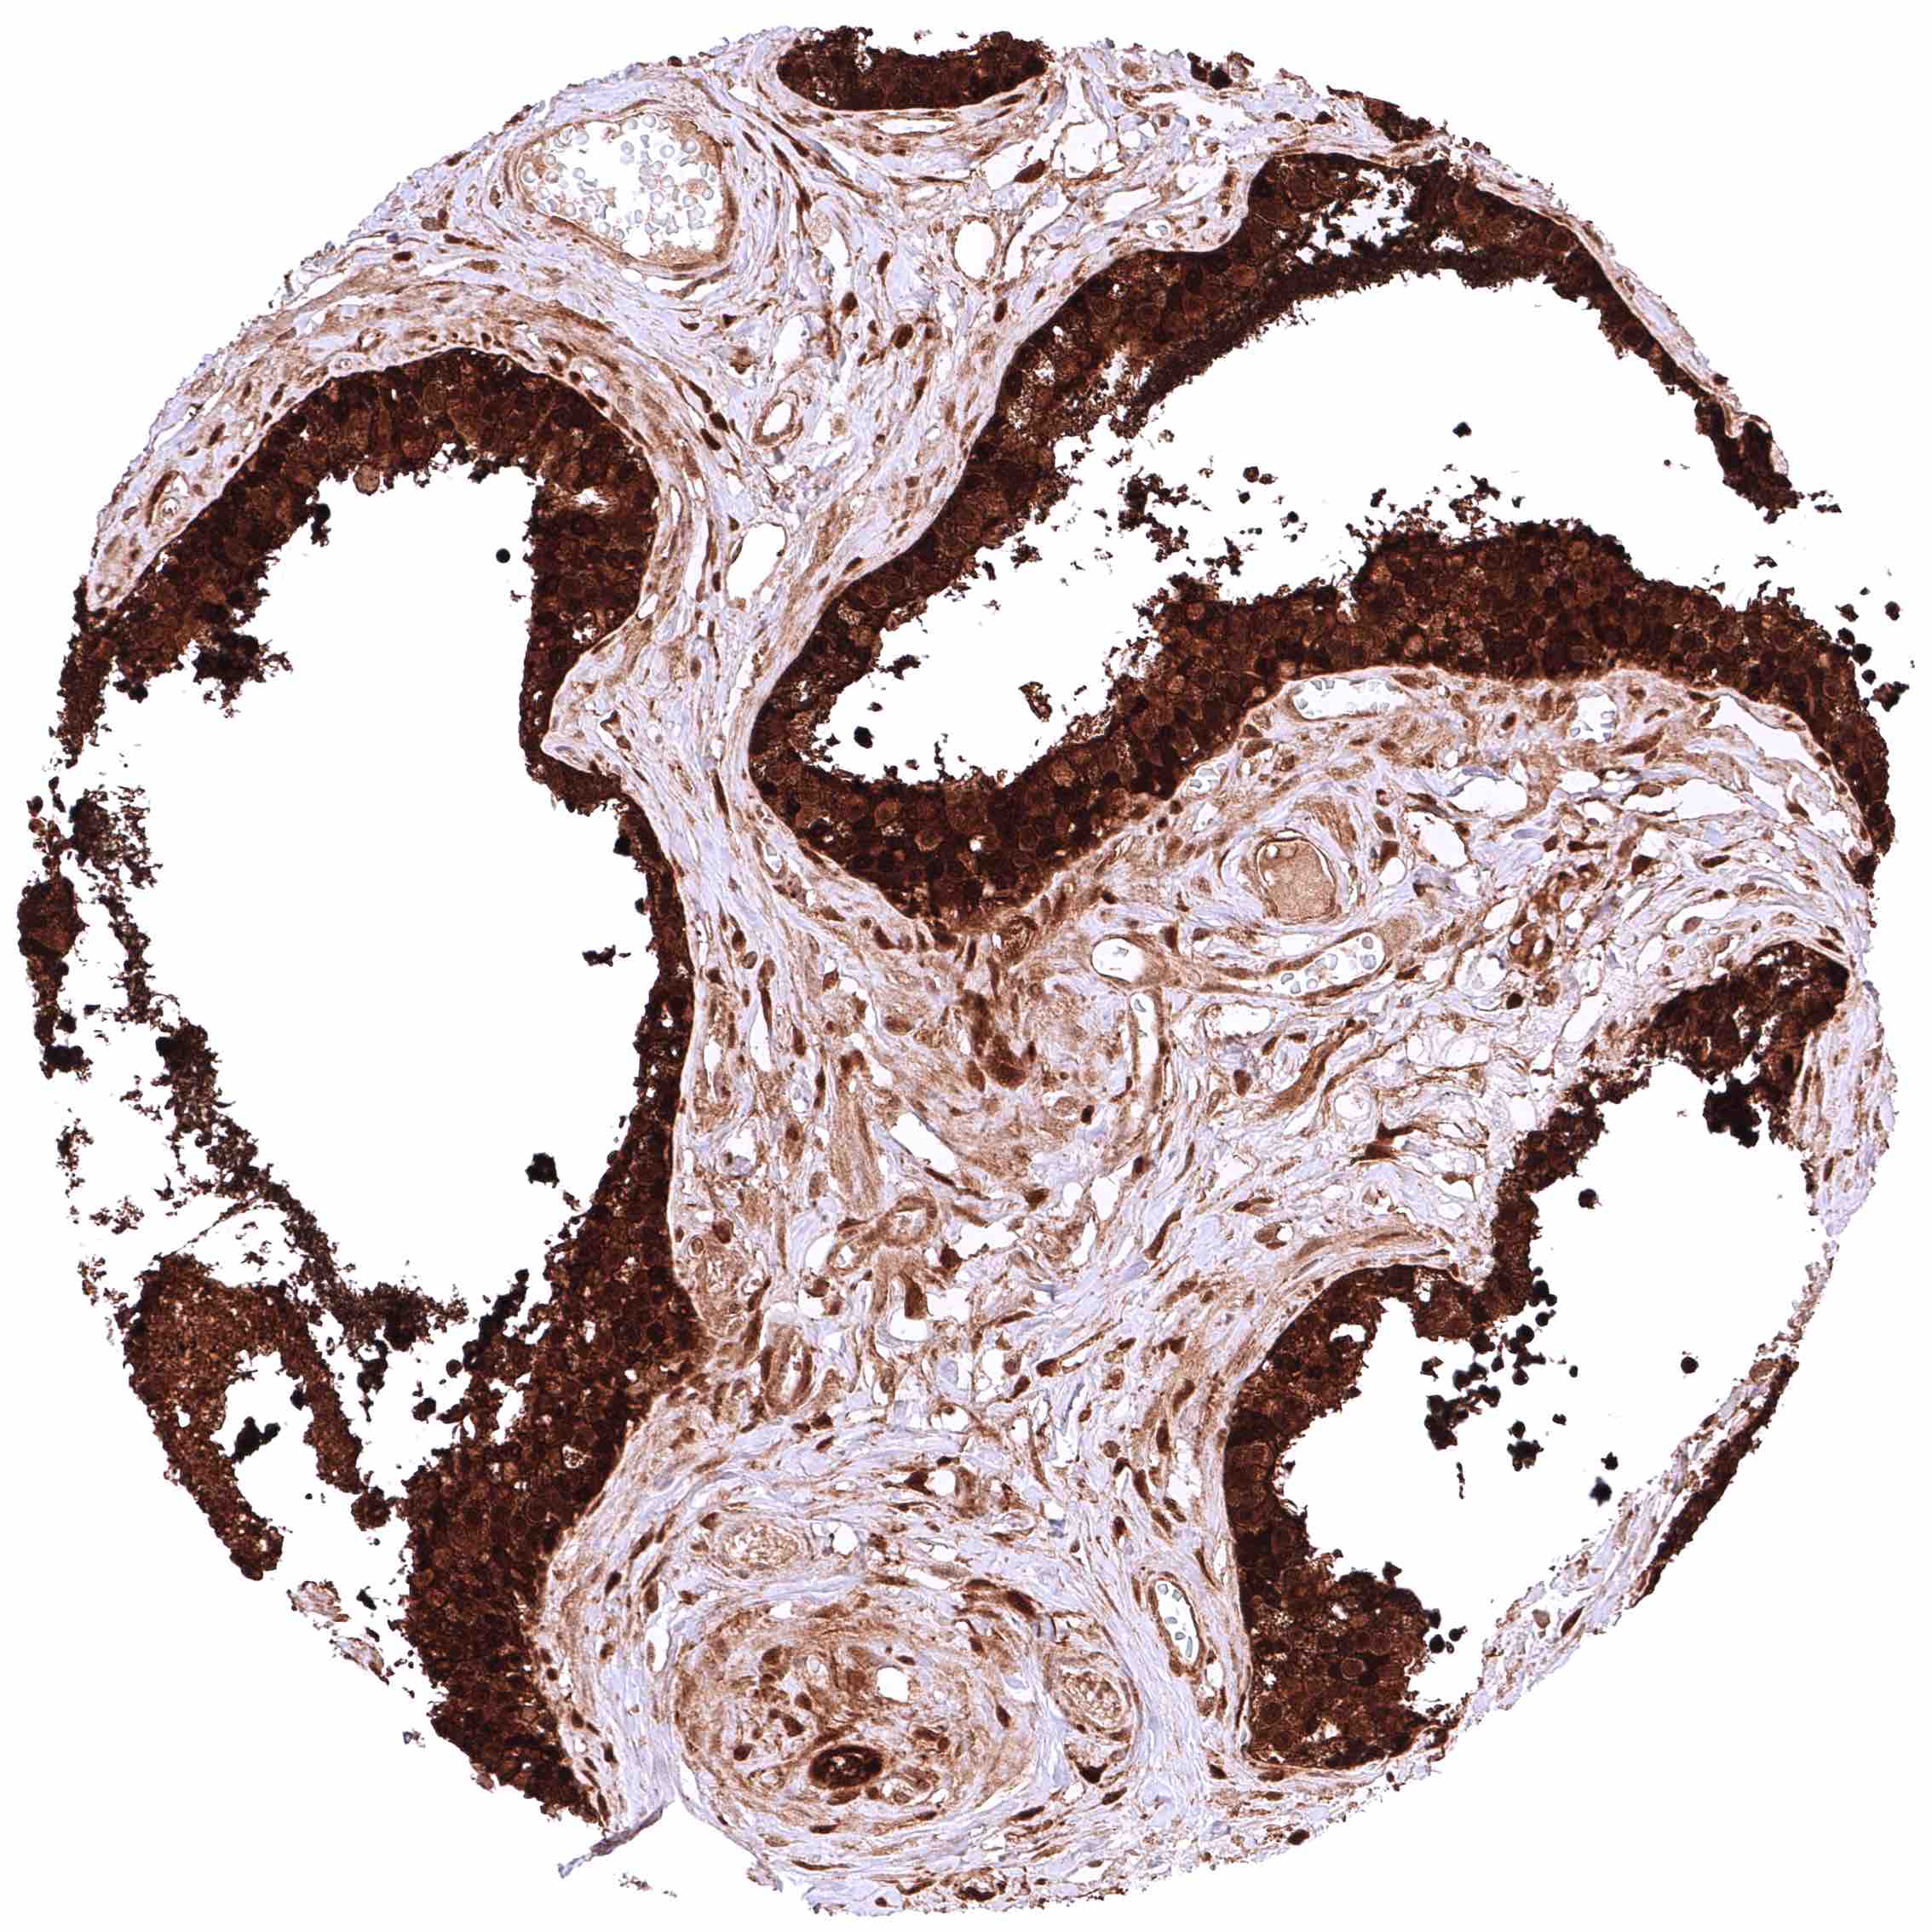

Skin – Strong nuclear and cytoplasmic GSTP1 positivity of all squamous epithelial cells.

Skin, ekkrine glands – Strong GSTP1 positivity of eccrine glands.

Skin, hairfollicle and sebaceous glands – Strong GSTP1 positivity of hair follicles and peripheral germinative cells of sebaceous glands while sebaceous cells remain GSTP1 negative.